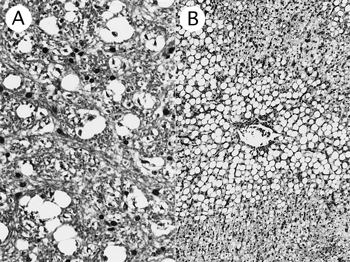

組織学的には,延髄白質に大小不規則な空胞が多数確認された(図8A).空胞は延髄から小脳,中脳四丘体で確認されたが,大脳ではほとんど確認されなかった.肝臓では,小葉中心性に空胞形成が認められ,肝細胞の変性や壊死巣も認められた(図8B).腎臓では,糸球体の梗塞および出血,尿細管の空胞形成および壊死が認められた.脾臓では,褐色色素の高度な沈着がみられ,空胞も散見された.

図8

A: 延髄白質の空胞変性(HE染色 ×200).

B: 小葉中心性の肝細胞空胞形成(HE染色 ×50).